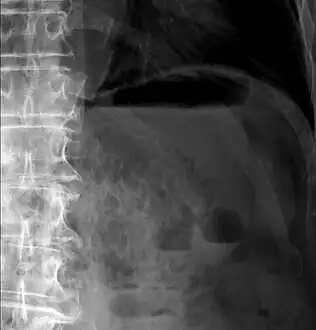

| Close-up of intestine of infant showing necrosis and pneumatosis intestinalis (autopsy) | |

Alimentary tract of infant showing intestinal necrosis, pneumatosis intestinalis, and perforation site (arrow) (autopsy)